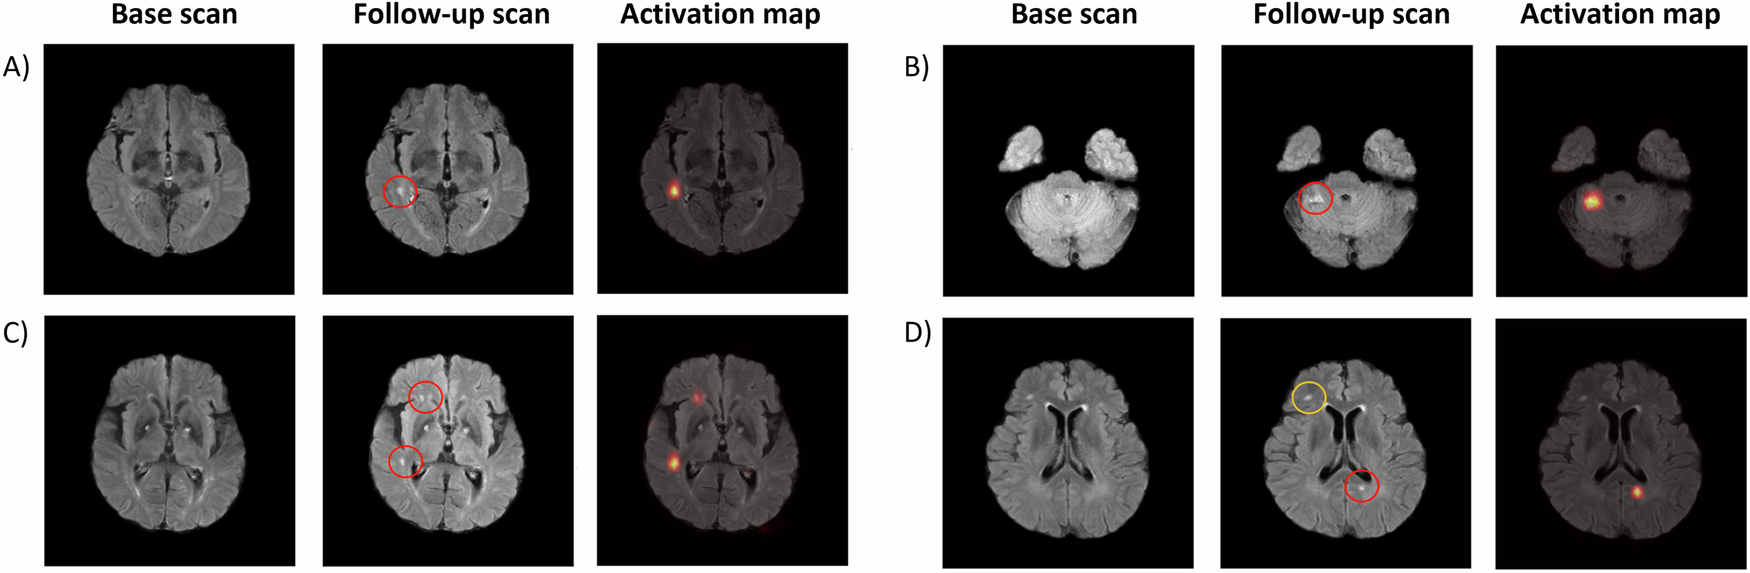

연구팀은 초기 MRI와 추적 MRI를 함께 입력으로 활용하는 시계열 기반 딥러닝 모델을 구축하였으며, FLAIR MRI를 중심으로 미세 병변 탐지 성능을 평가하였다. 그 결과, 제안된 모델은 다양한 임상 데이터에서 높은 정확도로 새로운 뇌경색을 탐지하였으며, 임상적으로 간과되기 쉬운 작은 병변에서도 유의한 성능을 보였다.

초기 및 추적 MRI에서 새롭게 발생한 뇌경색 병변과 인공지능 모델의 탐지 결과를 비교한 예시 (출처: Cho et al., npj Digital Medicine, 2026, CC BY-NC-ND 4.0)

또한, 새롭게 발생한 뇌경색의 존재 여부가 환자의 향후 임상 경과와 통계적으로 유의한 연관성을 보이는 것으로 나타나, 인공지능 기반 시계열 MRI 분석이 뇌졸중 환자의 예후 예측 및 장기 관리에 활용될 가능성을 확인하였다.